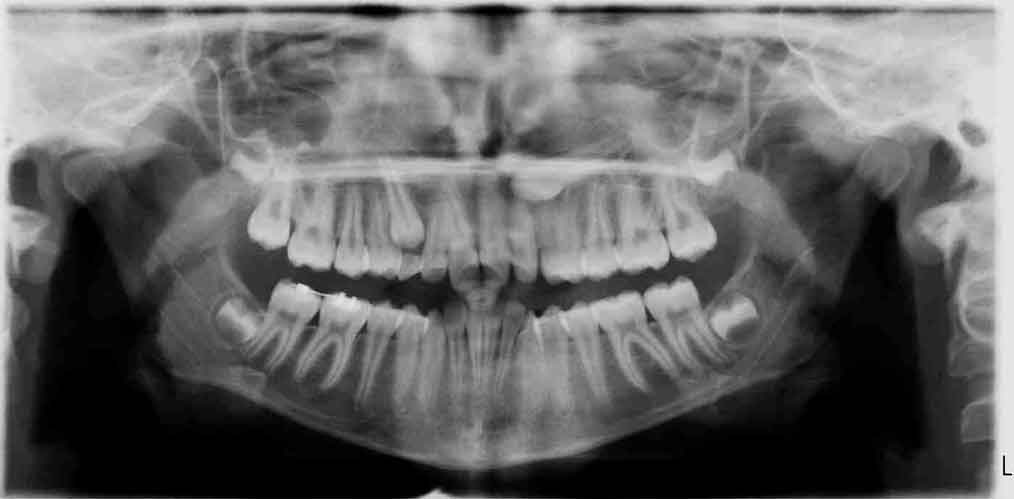

Caninos Impactados

En las siguientes imágenes puedes ver distintos resultados del tratamiento, deslizando la barra central de un lado a otro.